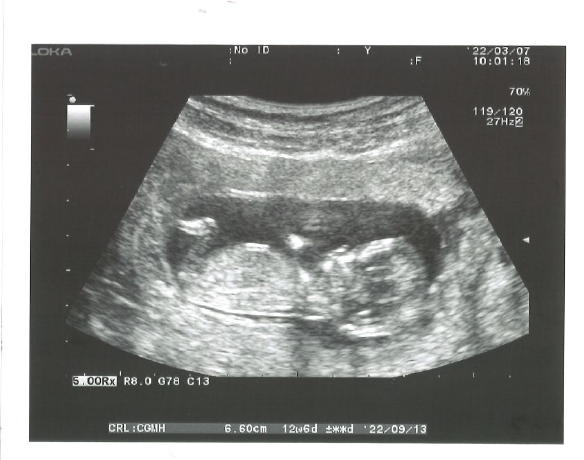

本想著年紀漸長卵巢功能又比較虛弱,讓自己放鬆些趁這段時間把子宮的狀況調養更好,再決定是否做試管? 過了幾個月,真的懷孕了!感到很喜悅也因為有先前的努力,所以成功了!只要有努力一定會有收穫的一天~加油

感謝黃醫師及醫護人員的照顧 結婚以來一直都是用順其自然的態度進行,一年拖過一年肚皮始終沒動靜。之後從網路搜尋到黃建榮婦產科,便決定在這兒繼續我的求子之路了! 剛開始也是吃口服排卵藥配合自然受孕方式治療,試了三次依舊沒有好消息…黃醫師建議可以做人工受孕試試看,受孕機會也比較高,但是試了二次後,還是沒有好結果,心情真得很沮喪…. 該做的治療就算害怕我也是硬 ...